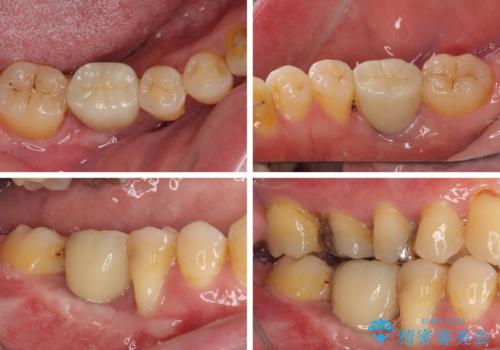

放置したことで炎症による骨吸収が顕著であるため、骨造成を併用してインプラント埋入を行うこととしました。

骨造成や歯肉移植など、治癒期間の長い処置を必要としたため治療期間は長くなりましたが、安定した咬み合わせと整った歯列となり、患者様には大変満足していただきました。